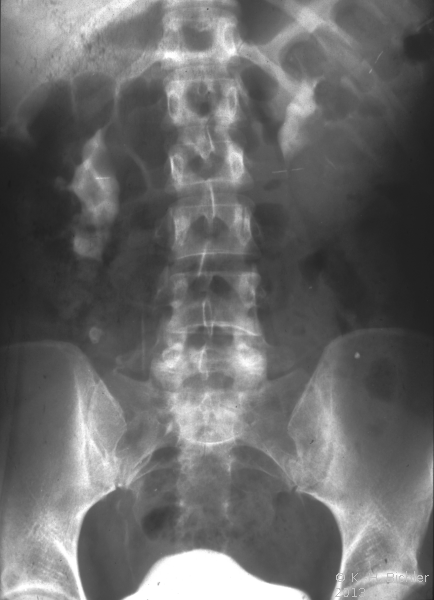

• Abbildung 19:

2. Nach Ureterabgangsplastik